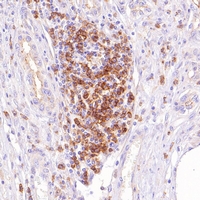

Immunohistochemical analysis staining in human liver carcinoma formalin fixed paraffin-embedded tissue section. The section was pre-treated using pressure cooker heat antigen retrieval with sodium citrate buffer (0.01M, pH=6) for 3 minutes. The section was detected using mouse primary antibody, and Goat Anti-Mouse/Rabbit IgG (H&L)-HRP polymer (Ready to use). The section was then counterstained with haematoxylin and mounted with Neutral Gum. -

Immunohistochemical analysis staining in human liver carcinoma formalin fixed parAcalephFluorfin-embedded tissue section. The section was pre-treated using pressure cooker heat antigen retrieval with sodium citrate buffer (0.01M, pH=6) for 3 minutes. The section was detected using rabbit primary antibody, and Goat Anti-Mouse/Rabbit IgG (H&L)-HRP polymer (Ready to use). The section was then counterstained with haematoxylin and mounted with Neutral Gum.